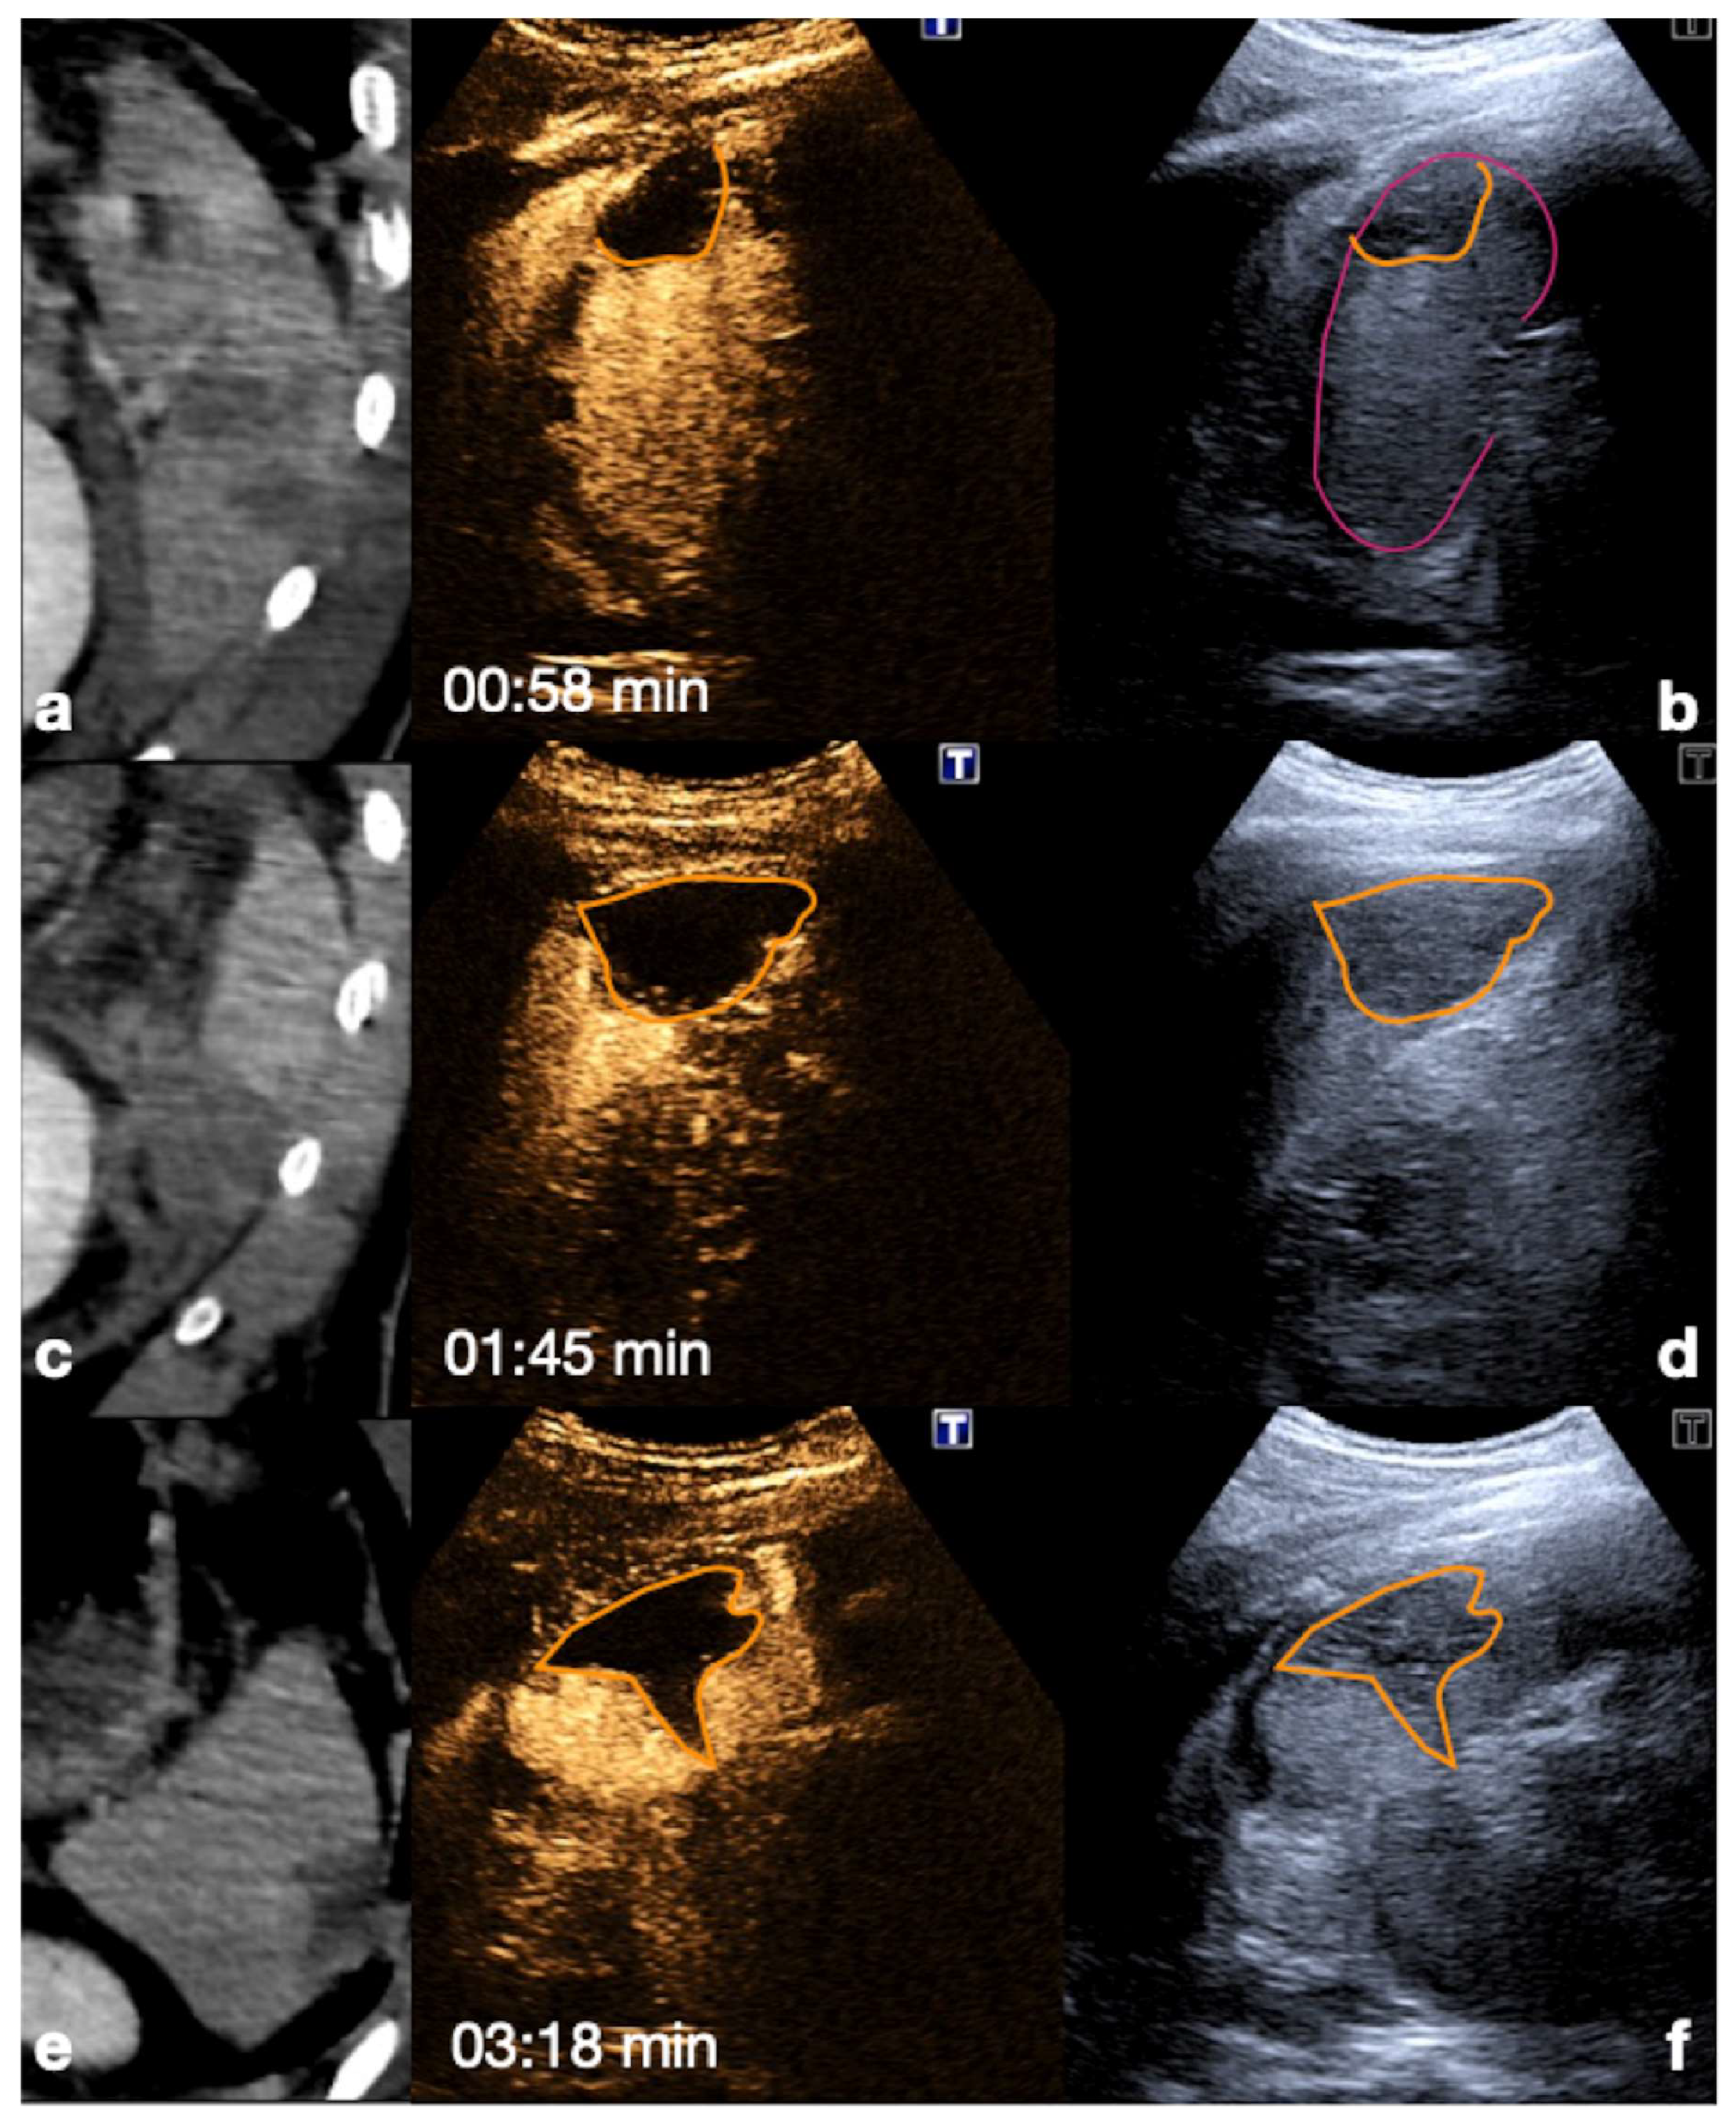

Figure 15.

Admission CT (a,c,e) and follow-up CEUS (b,d,f) of the spleen in a 35−year-old patient after a fall from height. Follow-up CEUS was performed seven days after the CT. Note at CEUS the progressive enhancement, at different time points, of the healthy spleen parenchyma in venous phase, clearly demarcated from the subcapsular hematomas (b, orange line), from the contusion of the inferior-pole (d, orange line) and from a sub-capsular laceration (f, orange line). Adopted from ref. [30], 2021, Iacobellis, F.; et al.